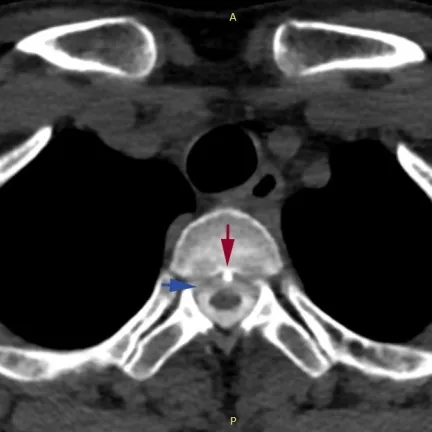

图片说明:骨刺刺破硬脊膜,导致脑脊液外漏的示意图

此前,浙江大学医学院附属邵逸夫医院神经内科也曾接连接诊过不少因长时间低头用电脑、玩手机而头痛难忍的年轻的“低头族”。经医院检查显示,患者颈段椎间盘退变,形成骨刺并刺破了硬脊髓膜,造成了脊髓脑脊液渗漏,颅内压力过低还造成了脑膜血管撕裂和硬膜下出血。

患者的脊柱磁共振检查,可见第2、3胸椎之间有“骨刺”形成,刺破硬脊髓膜,造成脑脊液外漏。